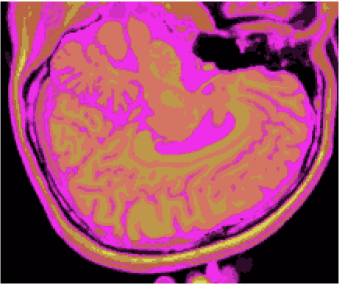

Figures 1 (band 0), 2 (band 1) and 3 (band 2) show PD- (proton density), - and -weighted MR images of the 97th slice, while figure 4 shows the R0-G1-B2 colored composition of the same slice.

Figures 5, 6, 7 and 8 show classification results, whilst figures 9, 10, 11 and 12 exhibit quantization results for the image of the 97th slice, figure 4, using methods KO, CM, KM and ODC, respectively. Image quantization is the procedure of constraining a determined image from its complete set of pixels to a smaller set of vectors with same dimensions feasible to represent the original image with a smaller gamute, according to a given fidelity measure. Herein this work we built quantization images just by changing the original pixels for the vectors of weights related to the classification results, i.e. the centroids of the unsupervised classification methods.